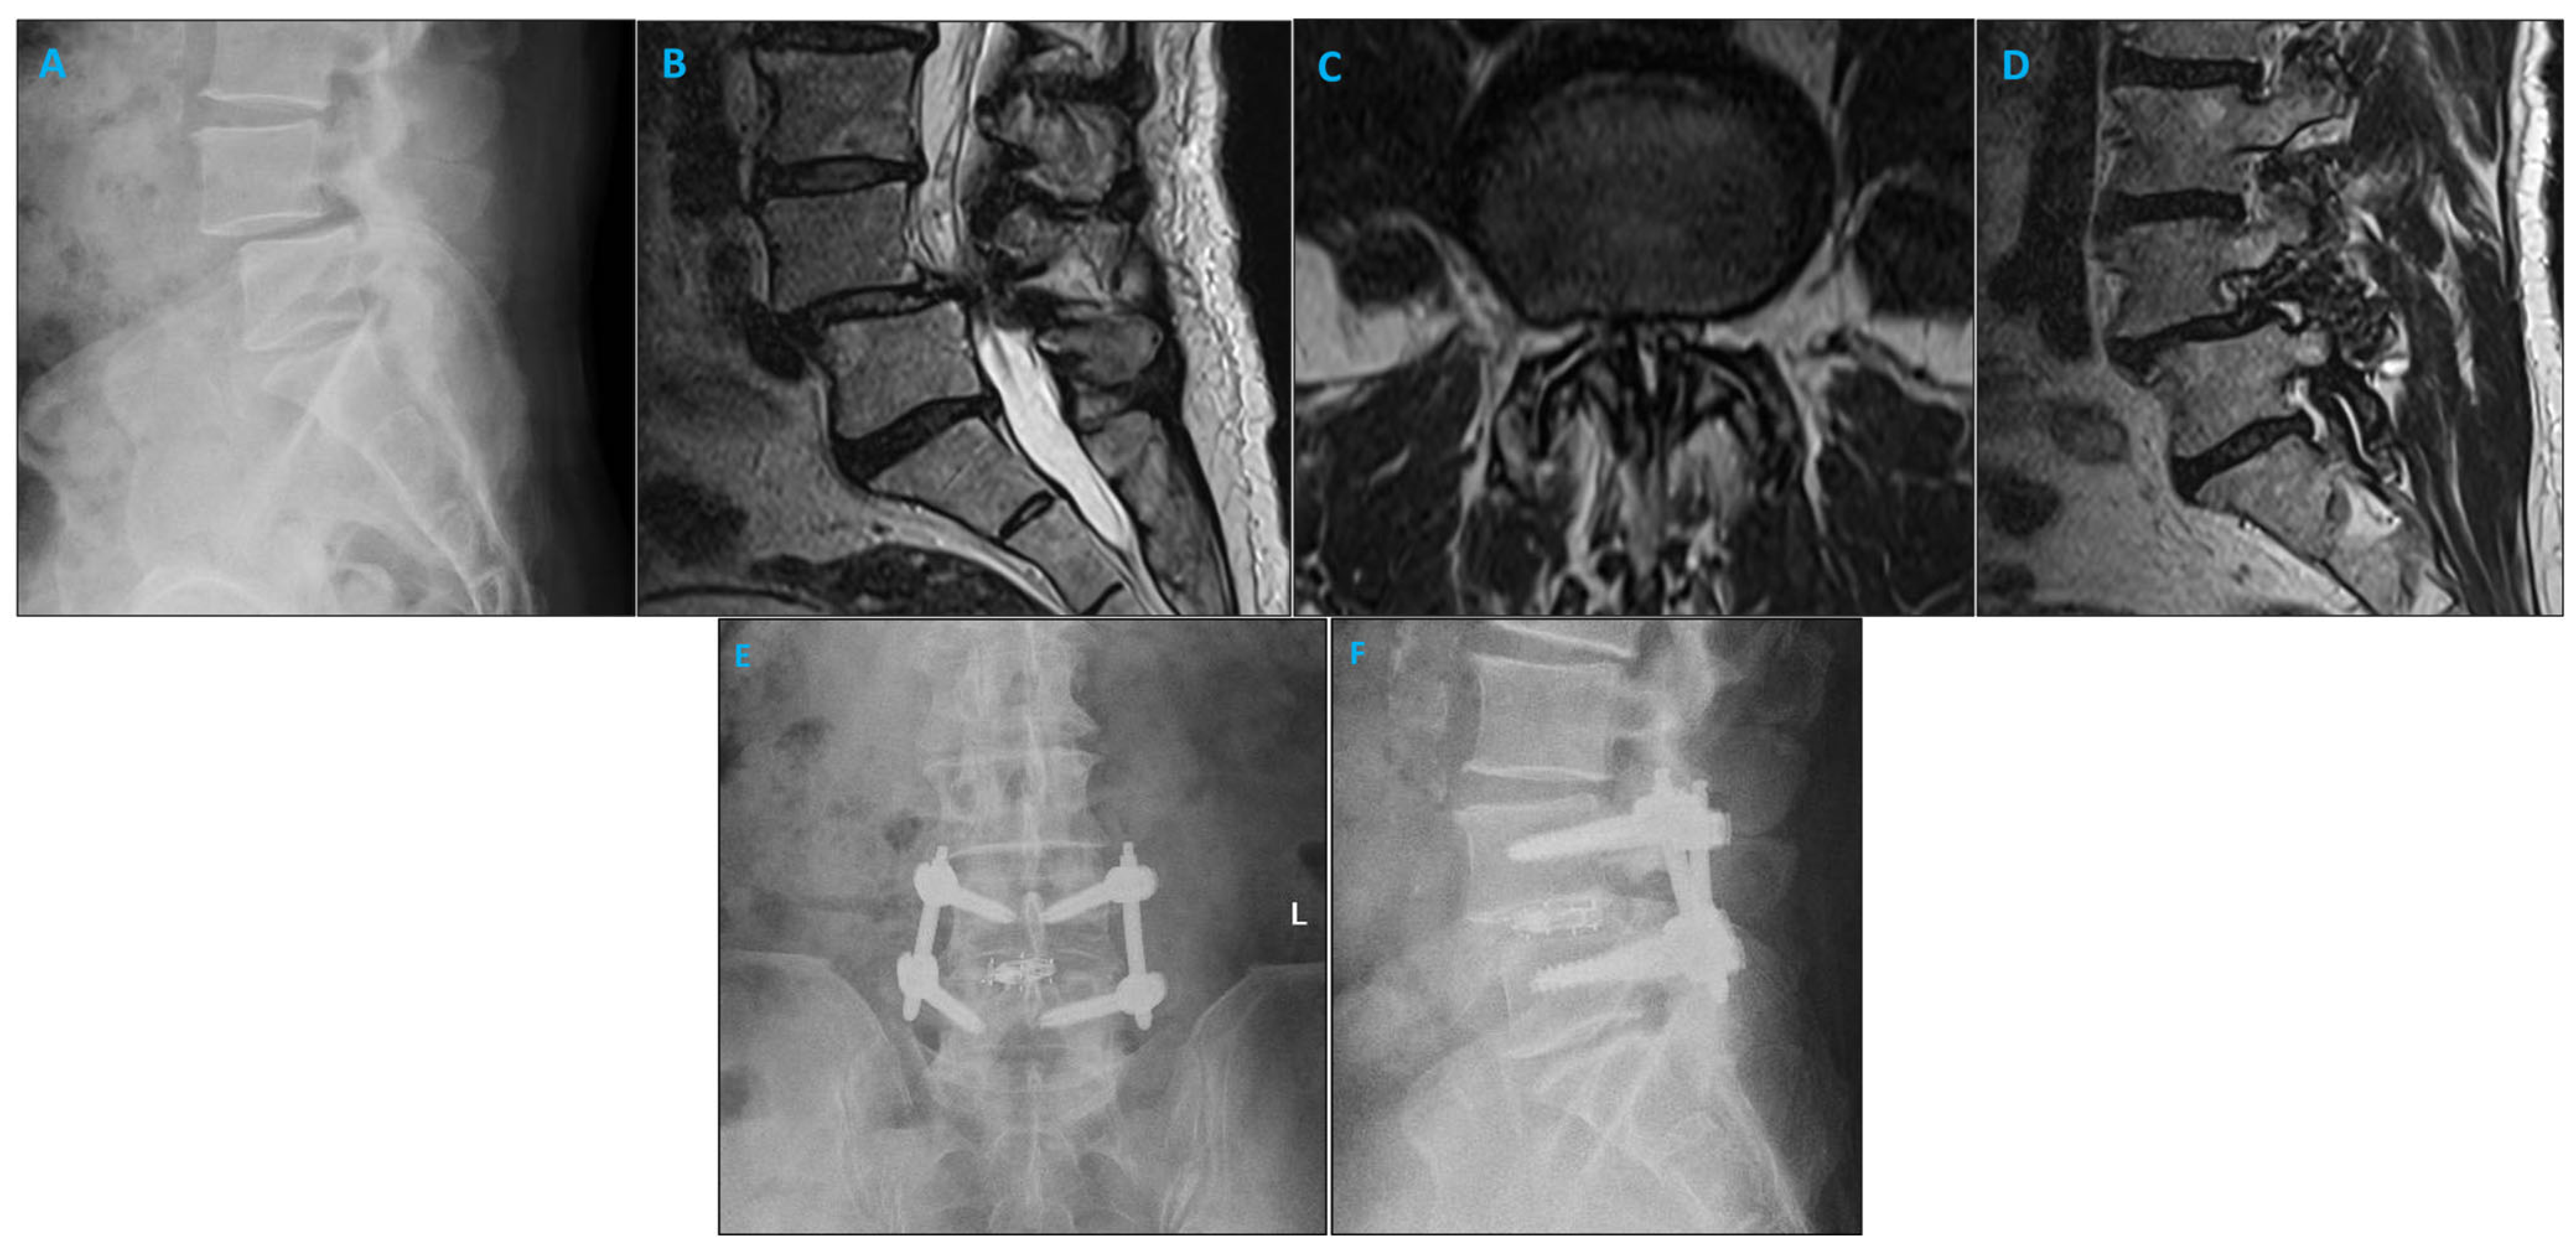

2.2. Surgical Approach

3.1. Patient and Surgery Characteristics

3.2. Screw Placement and Accuracy